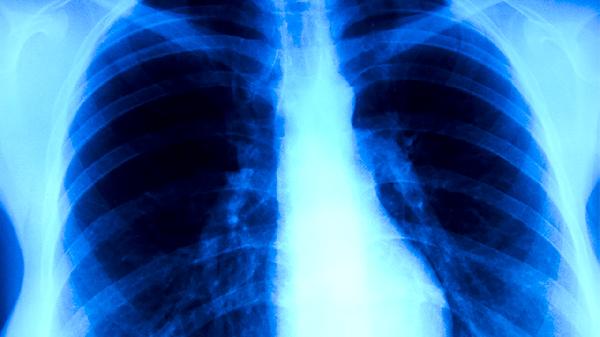

春天里花粉飘散,有人打喷嚏流泪,有人却咳得停不下来。别急着把所有咳嗽都归咎于过敏,有一种老牌传染病依然在悄然传播——肺结核。这种曾经在文学作品中被称为"白色瘟疫"的疾病,如今已不再是不治之症,但依然偏爱特定人群。